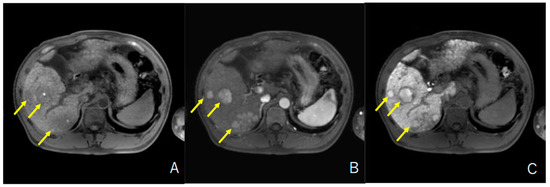

2.3. Evaluation of HCC with Iso-High Intensity in the Hepatobiliary Phase of EOB-MRI

3.2. Prevalence and Characteristics of HCC with Iso-High Intensity in the Hepatobiliary Phase of EOB-MRI in Patients with Unresectable HCC Who Were Treated with Lenvatinib